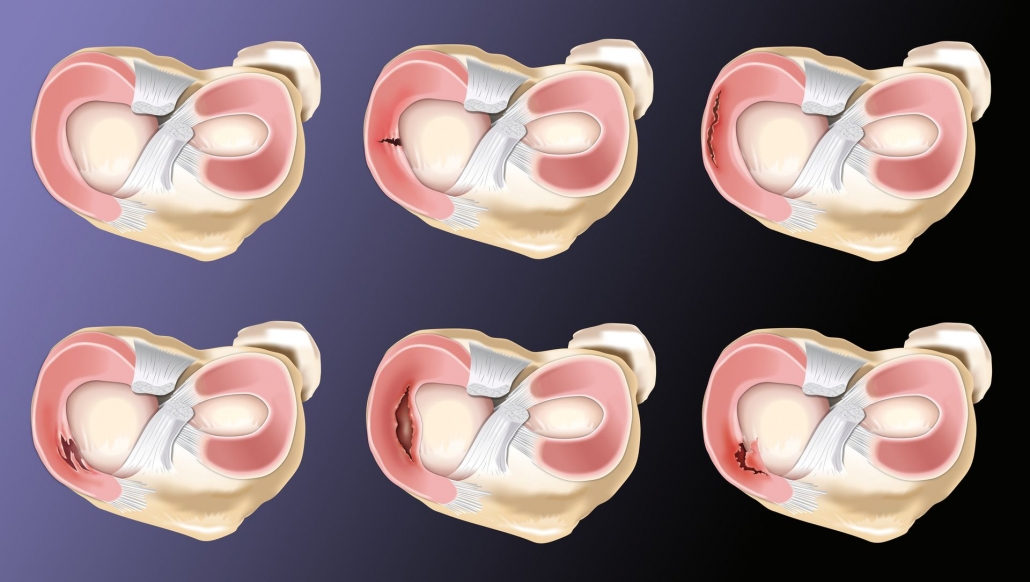

Desde que se introdujo la resonancia magnética nuclear como método de estudio radiológico en la década del 80, la manera de ver las estructuras de la rodilla y en especial los meniscos se ha ido modificando y ha permitido una precisión diagnóstica muy alta. Podemos ver los meniscos normales, su forma anatómica, sus variantes (como los meniscos discoides) y sus lesiones. Dentro de las lesiones meniscales, podemos detectar con una alta precisión el tipo de lesión de la que se trata: roturas radiales, longitudinales, horizontales, lesiones de la raíz meniscal, lesiones en rampa meniscal, lesiones con desplazamiento de fragmentos meniscales.

MR Imaging–based Diagnosis and Classification of Meniscal Tears